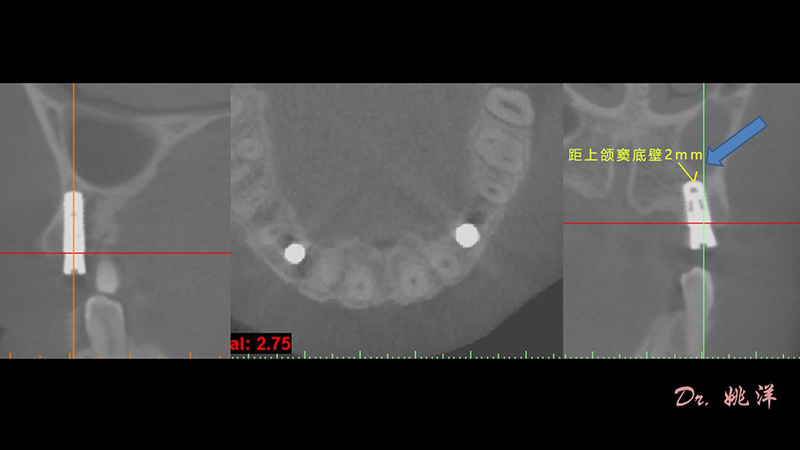

冠狀面視圖

矢狀面視圖

軸狀面視圖

根據(jù)患者CT顯示,使用種植導(dǎo)航軟件設(shè)術(shù)前手術(shù)方案??紤]到患者拒絕手術(shù)摘除上頜竇囊腫等因素,此次手術(shù)選用了Straumann骨水平4.10*8.0mm的植體,植體末端位點(diǎn)設(shè)計(jì)距上頜竇底壁2mm處的同時(shí)兼顧種植方向和修復(fù)間隙,來(lái)達(dá)到理想的效果。

從術(shù)后CBCT顯示可以看出,手術(shù)操作中完美地避開(kāi)上頜竇底,并兼顧了正確的種植方向和修復(fù)間隙